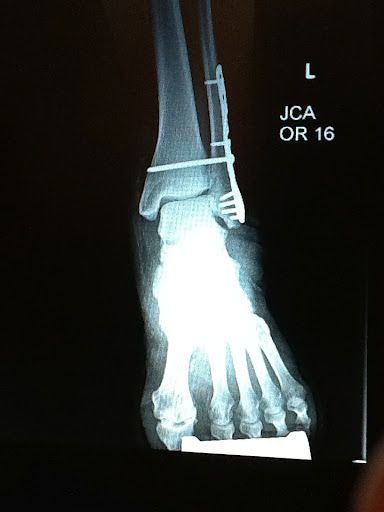

<==  Technically she dislocated her ankle and broke her fibula. They had the dickens of a time trying to get everything back into the right position at the emergency room.

She got some nice new hardware to help keep everything together: a plate and seven screws.

After 12 weeks the big long screw was removed and we now have it as a memento.